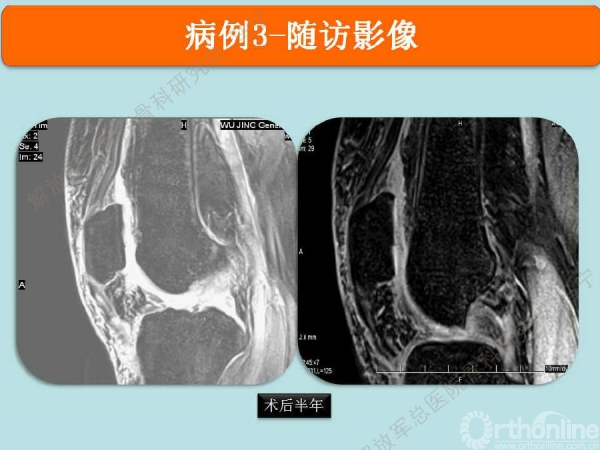

病例-3

双侧髌骨软骨同时损伤,同时做的软骨移植,双侧同时做目前在技术上没有问题,但术后康复起来会比只做单侧要时间长一些。